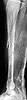

tibia

The patient came to me two days after injury. Her general condition was not good with Hb 6.7 gm%. After Blood transfusions in the first stage I did standard femoral Interlocking - 10mm nail with two proximal screws. 3 days later I did Tibial and Humeral Interlocking nailing - 8mm and 6mm nail respectively with proximal locking only.

On discharge 10 days later she wass walking independently with Zimmer frame with full knee hip and shoulder movements. Xrays are attached.